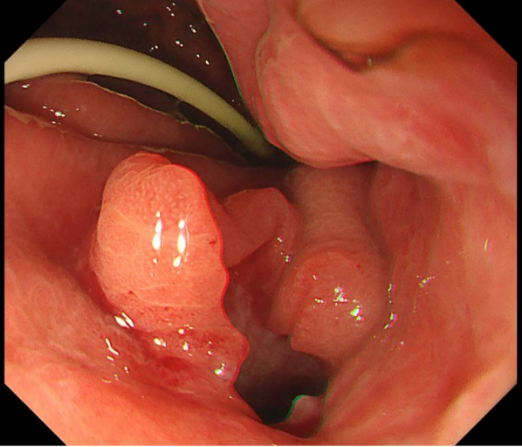

为确保引流充分持久,孙家琛创新性地在LAMS支架内,再叠加置入一枚“双猪尾”塑料支架,构建了一个独特的“双保险”引流结构——两个支架互为补充,即使其中一个出现堵塞,另一个仍能维持引流。这一设计,极大提升了长期引流的稳定性与通畅性。

内镜下操作在LAMS支架内,叠加置入“双猪尾”塑料支架,构建独特的“双保险”引流

左图术后4天,可见大量坏死物堵住支架,“双支架”发挥重要作用;右图术后4周,支架、营养管位置良好,包裹性坏死腔内新鲜肉芽组织

左图取出支架后经胃观察包裹性坏死腔,为新鲜肉芽组织;右图胃镜观察取出支架后的创面